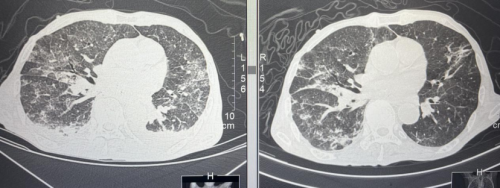

抗结核后复查胸部CT较前好转。